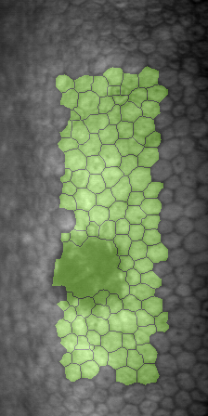

Specular microscopy assessment of the human corneal endothelium (CE) in Fuchs' dystrophy is challenging due to the presence of dark image regions called guttae. This paper proposes a UNet-based segmentation approach that requires minimal post-processing and achieves reliable CE morphometric assessment and guttae identification across all degrees of Fuchs' dystrophy. We cast the segmentation problem as a regression task of the cell and gutta signed distance maps instead of a pixel-level classification task as typically done with UNets. Compared to the conventional UNet classification approach, the distance-map regression approach converges faster in clinically relevant parameters. It also produces morphometric parameters that agree with the manually-segmented ground-truth data, namely the average cell density difference of -41.9 cells/mm2 (95% confidence interval (CI) [-306.2, 222.5]) and the average difference of mean cell area of 14.8 um2 (95% CI [-41.9, 71.5]). These results suggest a promising alternative for CE assessment.